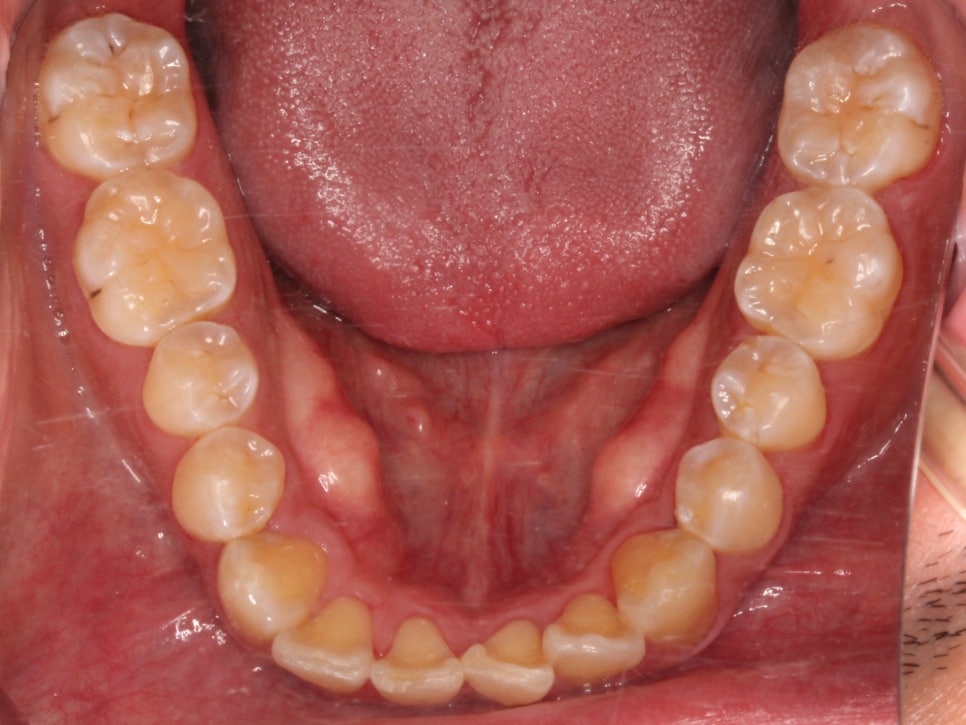

아래 앞니도 공간이 부족해서

약간 삐뚤빼뚤한 모습이 나타나지만

충분히 비발치 부분교정으로

펼칠 수 있는 케이스라 판단했습니다.